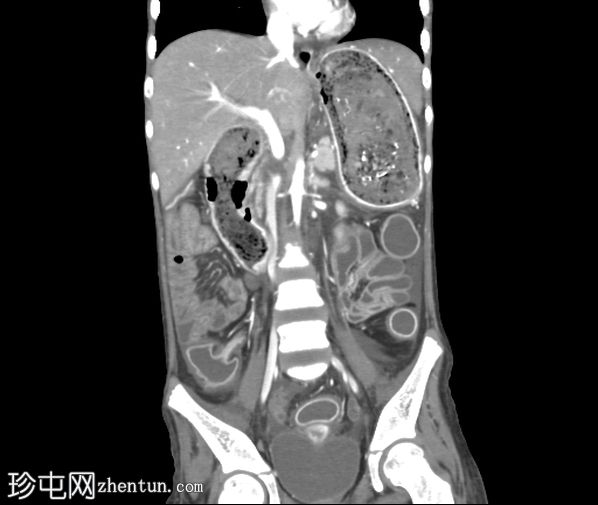

轴位增强扫描(门静脉期)

胃腔内可见巨大肿块,内含斑驳状软组织、气体和高密度灶,延伸至幽门、十二指肠和近端空肠(长发公主综合征)。十二指肠轻度扩张。

胃壁强化减弱及胃壁积气区域。